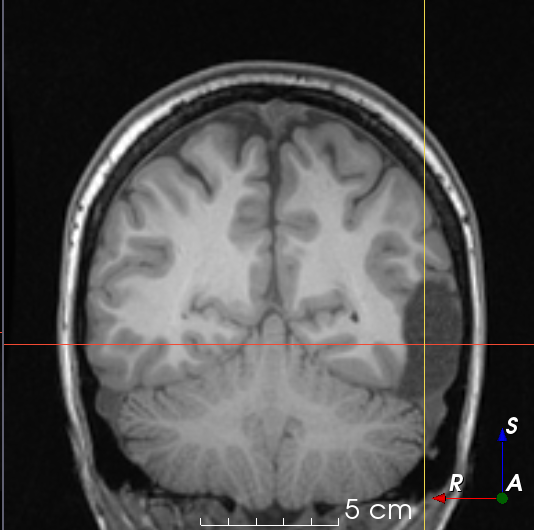

Refer to caption

(a)

(b)

(c)

(d)

(e)

(f)

(g)

(h)

Figure 6: Examples of challenging images for cavity segmentation. (a) Small frontal lesionectomy surrounded by hypointense white matter (b) Brain shift after contralateral temporal lobectomy (not shown) (c) Small frontal lesionectomy near the Sylvian fissure (d) Lack of boundaries between oedema and resection cavity (e) Possible blood clot within the cavity (f) Brain shift, oedema and resection cavity (g) Arachnoid cyst and resection cavity (h) Cerebellar degeneration. Green annotations represent areas that correspond to resection cavities; red annotations represent areas that do not.

Predictions errors are mostly due to 1) resection of size comparable to sulci (Fig. 6a), 2) unanticipated intensities, such as those caused by the presence of blood clots in the cavity (Fig. 6b), 3) brain shift (Fig. 6c) and 4) white matter hypointensities (Fig. 6e). Further work will involve using different internal and external cavity textures, carefully sampling the resection volume, simulating brain shift using biomechanical models, and quantifying epistemic and aleatoric segmentation uncertainty to better assess model performance [24].